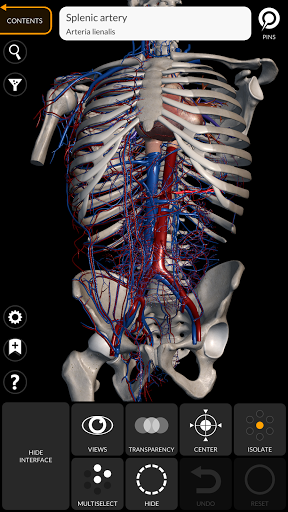

"Anatomy 3D Atlas" cho phép bạn nghiên cứu giải phẫu người theo cách dễ dàng và tương tác.

Thông qua giao diện đơn giản và trực quan, bạn có thể quan sát mọi cấu trúc giải phẫu từ mọi góc độ.

Các mô hình giải phẫu 3D đặc biệt chi tiết và có kết cấu lên đến độ phân giải 4k.

Việc phân chia theo vùng và chế độ xem được xác định trước giúp quan sát và nghiên cứu các bộ phận hoặc nhóm hệ thống riêng lẻ và mối quan hệ giữa các cơ quan khác nhau.

• Hệ thống tim mạch

• Tùy chọn ẩn hoặc cô lập một hoặc nhiều mô hình đã chọn

• Chức năng trong suốt

• Bằng cách chọn một mô hình hoặc một ghim, thuật ngữ giải phẫu liên quan sẽ hiển thị

• Các thuật ngữ giải phẫu có thể được hiển thị bằng hai ngôn ngữ cùng lúc